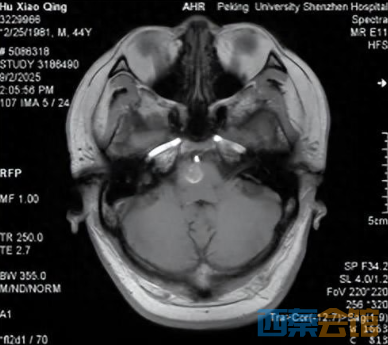

家人紧急将其送往医院,急诊检查结果让所有人揪心——头颅MRI显示,阿伟脑干桥脑右侧存在占位性病变,确诊为海绵状血管瘤并出血。

“脑干是人体的生命中枢,长约8厘米,最宽处仅2厘米,控制着心跳、呼吸、血压等基本生命功能,这个拇指大小的区域密布着关键神经与血管。”

医生介绍,海绵状血管瘤虽名为“瘤”,实则是异常扩张的血管团,约20%发生在脑干,致死和致残率极高,“每一次出血都可能导致灾难性的神经功能损伤,阿伟的肢体无力和言语障碍,说明出血已经影响到重要神经结构。”

ScreenShot_2026-03-06_163230_394.png ScreenShot_2026-03-06_163237_858.png